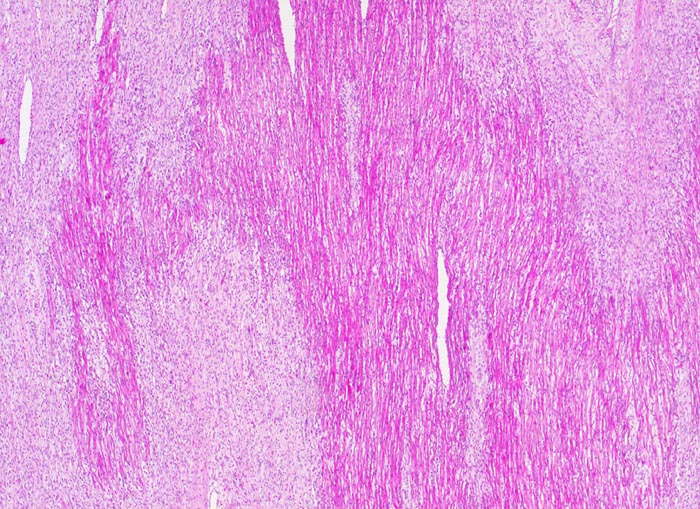

Subakute histiozytäre nekrotisierende Virusmyokarditis

Grobfleckige subakute Nekrosen (helle Areale).

Lymphohistiozytäre interstitielle Pneumonie.

Myokarditis mit kardiogenem Schock.

Trotz negativem Virusnachweis ist der Befund gut vereinbar mit einer viralen Myokarditis.